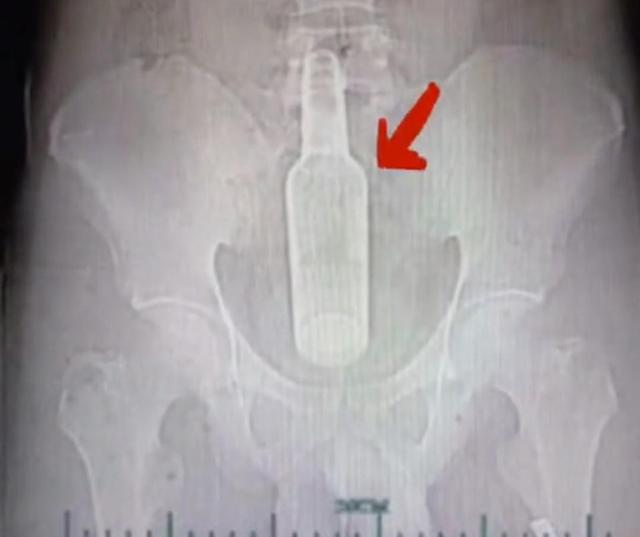

杭州一名小伙也是为了治疗便秘,竟然把一个花露水瓶子塞进了直肠里,无法取出向医生求助,医生费了很大的劲才把瓶子取出来。